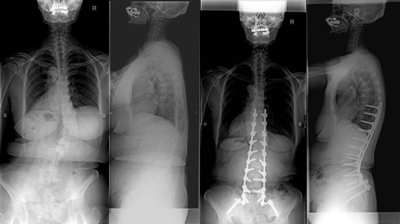

骨切りを併用した後方矯正固定術

せぼねの変形が大きかったり、再手術の場合には癒合してせぼねの骨切りを行い、再度矯正固定を行う場合があります。

5時間前後の長時間の手術となります。入院期間は小児患者様で2週間程度、大人の患者様では3週間程度で場合によってはリハビリテーション病院へ転院をしていただき、さらにリハビリテーションを行います。

腰椎固定術後後弯に対する椎体骨切り術を併用した後方矯正固定術